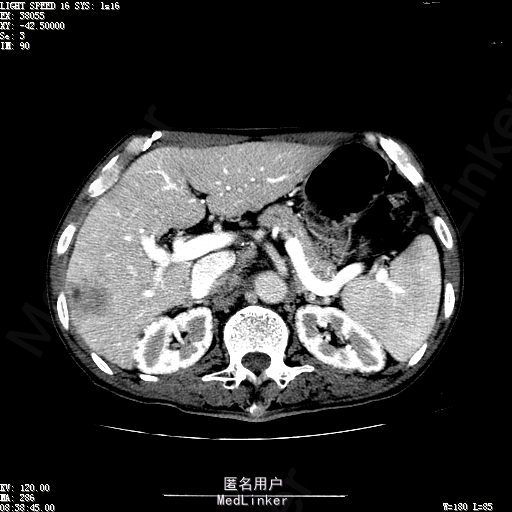

查体:体温36.3℃,脉搏76次/分,呼吸18次/分,血压120/80mmHg。神志清晰,肝病面容,皮肤粘膜颜色正常无黄染,全身皮肤未见皮疹、瘀点及紫癜,肝掌阳性,未见蜘蛛痣,浅表淋巴结未触及。巩膜无黄染,结膜正常。双肺呼吸音清,无胸膜摩擦音。心率:76次/分,心律齐,心音正常,无杂音,无心包摩擦音。腹平坦,无腹壁静脉曲张,未见胃肠型及蠕动波,双侧腹股沟可见手术瘢痕,脐部正常。触诊:无压及痛反跳痛,无腹肌紧张,无腹部包块。肝脾肋下未触及,Murphy征阴性,肾未触及,移动性浊音阴性。肝肾区叩击痛阴性,无脾区叩击痛。听诊:肠鸣音正常,4次/分,无气过水声。脊柱无侧弯,脊柱活动度正常,棘突正常,四肢正常,关节正常,无下肢水肿,无下肢静脉曲张,无杵状指趾。扑翼样震颤阴性。 门诊化验ALT9U/L,AST21U/L,HBVDNA<1.0E+03IU/mL,HBsAg1138IU/mL,WBC6.2x10^9/L,RBC3.92x10^12/L,PLT167x10^9/L,AFP28.95ng/ml,AFU 29U/L,彩超示肝右叶肝回声,大小约5.1*3.5cm,Fibroscan:脂肪变:163硬度10.8。 CT如下图

诊断:1、乙肝肝硬化 活动性 代偿期 原发性肝癌 2、胃溃疡 3、十二指肠球部溃疡 处理:血管介入治疗:手术者术前查看患者相关情况:化验回报:血细胞分析(五分类):*白细胞计数 8.1 10^9/L、*红细胞计数 4.00 10^12/L↓、*血小板计数 202.0 10^9/L、*血红蛋白 136 g/L,肝功酶谱:*丙氨酸氨基转移酶 5 U/L、天门冬氨酸氨基转移酶 22 U/L、*白蛋白 37.6 g/L、*总胆红素 17.8 umol/L,肾功能检测:*尿素 5.79 mmol/L、*肌酐 67.1 umol/L,凝血五项:凝血酶原时间 10.7 秒↓、凝血酶原百分活动度 93.3 %,甲胎蛋白测定:甲胎蛋白 30.30 ng/mL↑。患者病情平稳,今日术前准备,签署相关文件。 手术简要经过:患者平卧位,以右侧腹股沟区为中心常规消毒、铺巾、利多卡因局麻。改良Seldinger法逆行穿刺右侧股动脉成功,置入5F血管鞘。经血管鞘造影,见髂外动脉明显迂曲,经鞘送入超滑导丝,退出原5F血管鞘,换入5F长25厘米血管鞘。沿导丝送入肝管,将管头送入腹腔干,进一步送至肝右动脉。经正位、右前斜30°造影,明确肝右叶膈顶一处较大肿瘤染色,S5段一处较小肿瘤染色。以微导管超选S6段肝动脉干,经多角度造影明确为肿瘤供血动脉,注入混悬液(碘化油10毫升+雷替曲塞2毫克)3毫升,明胶海绵颗粒1/12支。再以微导管超选S7段肝动脉干,造影明确为肿瘤供血动脉,注入混悬液2毫升,明胶海绵颗粒1/20支。再以微导管超选S8段分支,造影明确为肿瘤供血动脉,注入混悬液2.8毫升,明胶海绵颗粒1/12支。再以微导管超选S5段肝动脉分支,造影明确为较小肿瘤供血动脉,注入混悬液0.8毫升,明胶海绵颗粒1/30支。退出微导管。经肝右动脉注入奥沙利铂100毫克。退出肝管。拔出血管鞘,局部压迫5分钟。加压包扎。